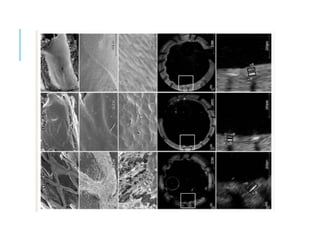

La ecografía intravascular es una nueva técnica

LO NUEVO EN HEMODINAMIA…IVUS

(A) muestra una imagen de escala de grises. (B) Muestra una imagen

histológico correspondiente.

LO NUEVO ENHEMODINAMIA…IVUS La ecografía intravascular es una nueva técnica angiografía invasiva , también a través de catéter se introduce un diminuto transductor. Actualmente se hace al final de una angioplastía para colocación de Stent. La diferencia con la angioplastía con solo rayos x es que esta no puede mostrar sus paredes. Las imágenes de la ecografía intravascular muestran las paredes de las arterias y pueden revelar la presencia de colesterol y depósitos de grasa (placas). La acumulación de estos depósitos puede aumentar el riesgo de un ataque cardíaco.

(A) muestra unaimagen de escala de grises. (B) Muestra una imagen análisis de los componentes. Esta placa está clasificado como un fibroateroma ya que tiene una capa fibrosa visible que cubre un núcleo necrótico confluentes más del 10%. (C) Muestra el corte histológico correspondiente. LO NUEVO EN HEMODINAMIA…IVUS